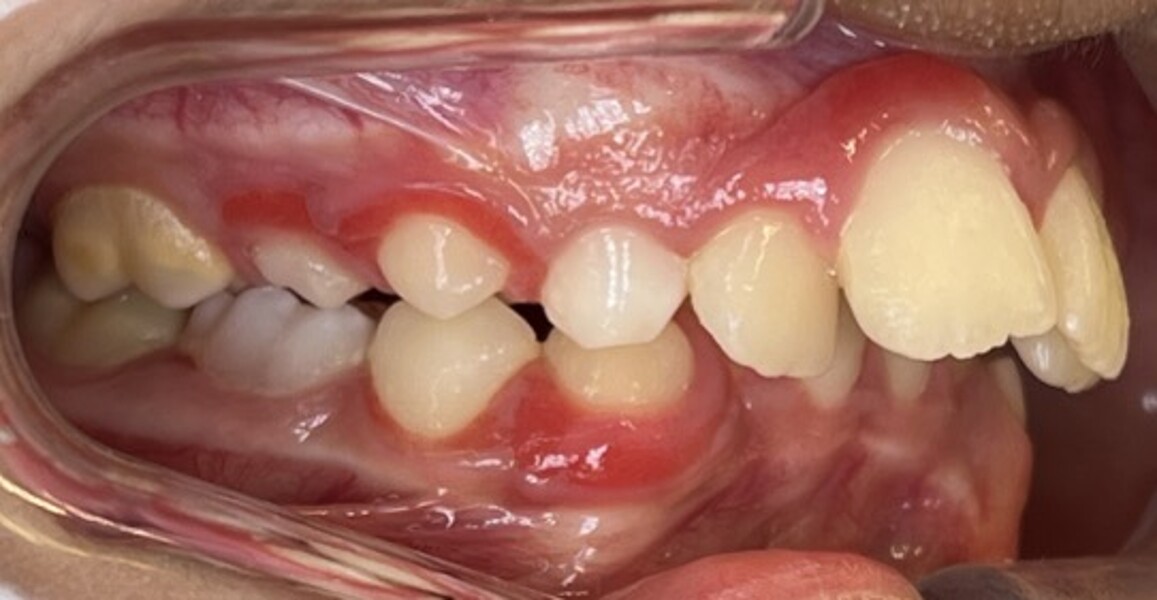

Figs. 6a–e: Intra-oral photographs after the first phase of treatment.

At the end of the first phase of treatment, the clinical findings included (Figs. 5 & 6):

Class I molar and canine relationships on the left side;

half-cusp Class II relationships on the right side;

normal overjet (2.0 mm) and overbite (2.5 mm); and

a posterior open bite, particularly on the left side.

Cephalometric analysis showed that the sagittal discrepancy had been significantly reduced (ANB = 3.7°; Wits = 1.8 mm). Mandibular length remained below normative values.